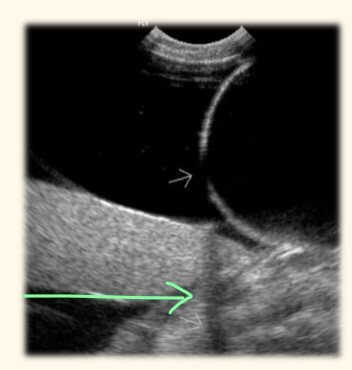

what is causing this line of hypoechogenicity